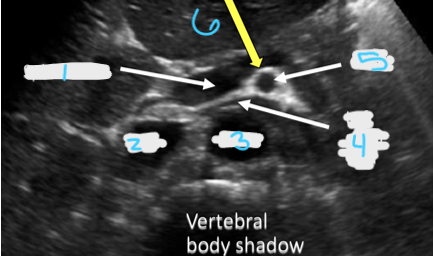

<p>In this transverse view, what is #1?</p>

In this transverse view, what is #1?

Aorta

<p>In this transverse view, what is #2?</p>

In this transverse view, what is #2?

Common Hepatic Artery

<p>In this transverse view, what is #3?</p>

In this transverse view, what is #3?

Left Splenic Artery

<p>In this transverse view, what is #4?</p>

In this transverse view, what is #4?

Left Renal Vein

<p>In this transverse view, what is #5?</p>

In this transverse view, what is #5?

SMA

<p>In this transverse view, what is #6?</p>

In this transverse view, what is #6?

Splenic vein